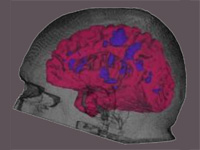

Generation of Connectivity-Preserving Surface Models of Multiple Sclerosis Lesions

In this article we introduce a software tool to build 3D surface models of Multiple Sclerosis (MS) brain lesions from 2D image stacks typically obtained through Magnetic Resonance Imaging (MRI). This tool allows users to create 3D models of MS lesions quickly and visualize the lesions and brain tissue using various visual attributes and configurations.

(journal article, online version @ google books, online version @ SHTI, reference).

Concurrent Visualization of and Mapping between 2D and 3D Medical Images for Disease Pattern Analysis

We present a software tool to highlight and display regions of interest in 2D medical images and their 3D mesh model counterparts. This tool can help researchers visualize and compare brain lesions and tissues in 2D and 3D at the same time.

(conference article, online article @ VBL, reference).